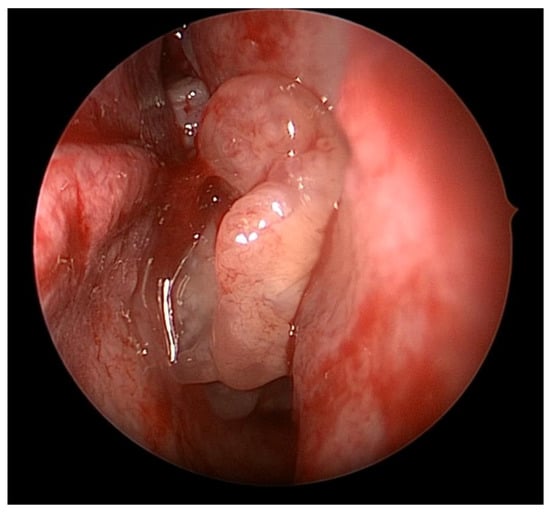

4. Surgical Planning

7.1. Endoscopic versus Open Surgery for IP

7.2. Attachment-Oriented Surgery

7.3. Surgical Techniques and Outcomes